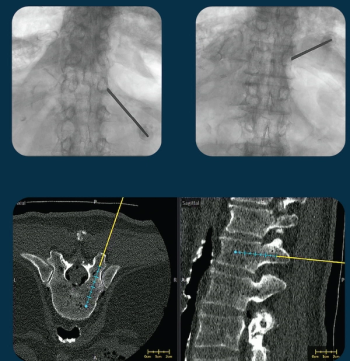

The second-generation version of the VUZE System reportedly offers expanded functionality and incorporation of varied sources of 3D imaging data, including cone-beam CT scans obtained in the OR.